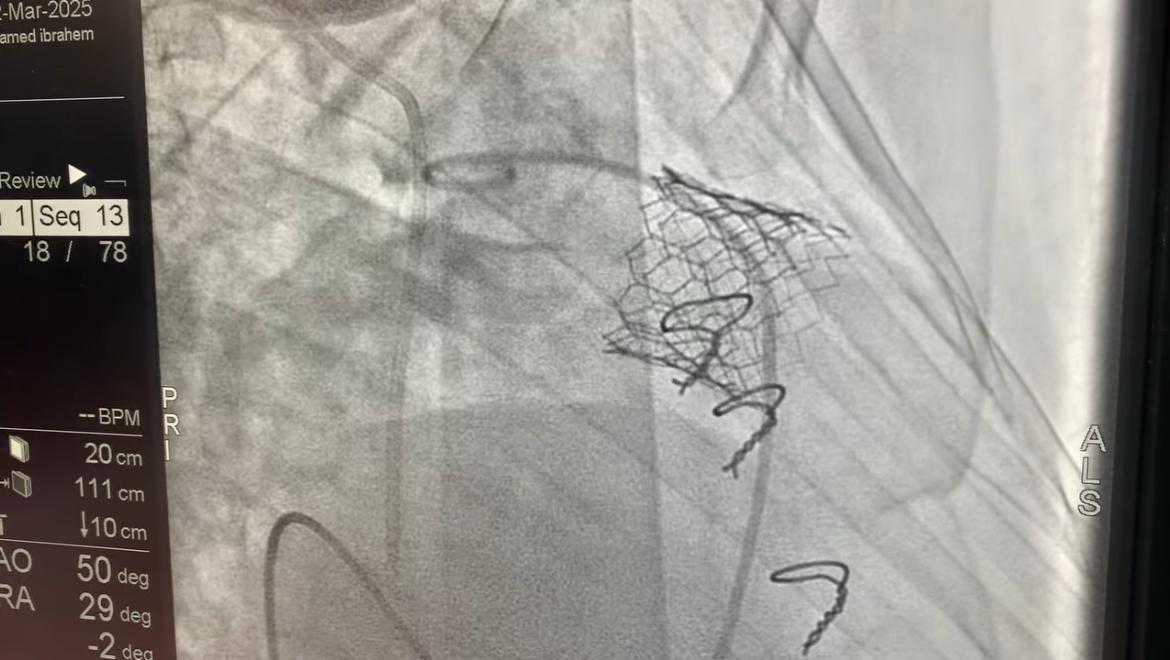

ومن جانبه، قال الدكتور محمد مصطفى عبدالغفار رئيس الهيئة العامة للمستشفيات والمعاهد التعليمية، أن زراعة الصمام الرئوي بالقسطرة تقنية حديثة تُمثل بديلًا آمنًا لجراحة القلب المفتوح، حيث يتم إدخال الصمام الجديد عبر قسطرة دون الحاجة إلى شق الصدر أو إيقاف القلب، مما يقلل بشكل كبير من المخاطر والمضاعفات.

واستكمل أن هذه التقنية تتيح تقليل فترة التعافي، بحيث يغادر المرضى المستشفى في غضون 24 إلى 48 ساعة فقط، بالإضافة إلى تجنب مخاطر الجراحة، مثل النزيف الحاد والعدوى وفترات النقاهة الطويلة، مما يؤدي إلى تحسين جودة الحياة للمرضى الذين يحتاجون إلى استبدال الصمام بعد جراحات القلب السابقة.